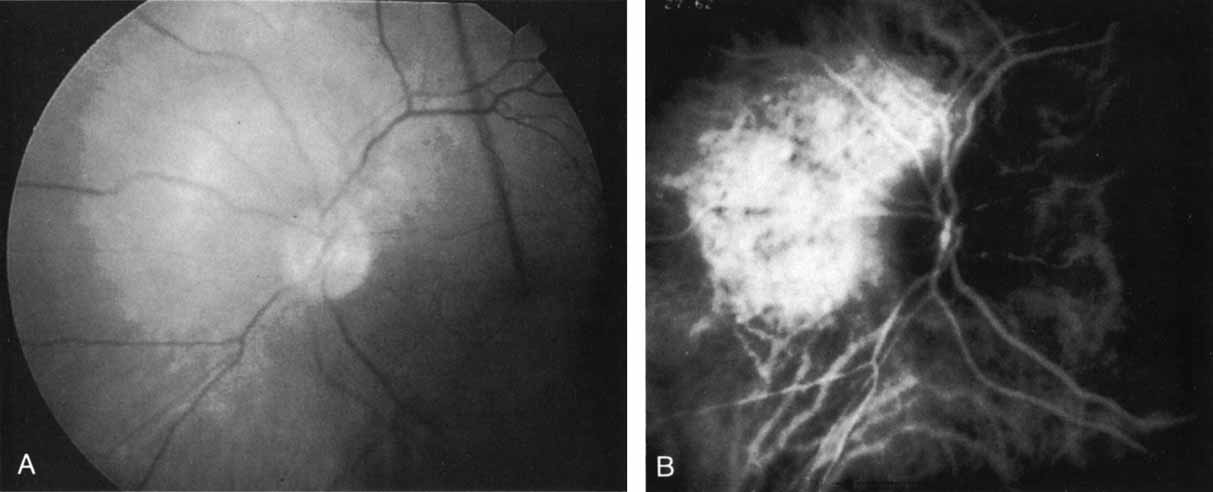

Idiopathic polypoidal choroidal vasculopathy, also known as posterior uveal bleeding syndrome, typically affects darkly pigmented persons who exhibit acute exudative manifestations in the posterior pole, including subretinal hemorrhage and, occasionally, CNV.76,77 ICG angiography facilitates a more definitive diagnosis than fluorescein angiography because it achieves a sharper image of the primary lesion,51,77,78 dilated choroidal vessels terminating in polypoidal or aneurysmal excrescences at the level of the choroid (Fig. 23). These vascular changes account for the secondary exudative and hemorrhagic detachments of the retinal pigment epithelium and neurosensory retina that are characteristic of this disorder. Furthermore, ICG angiography may provide a better means of differentiating the relatively benign aneurysm-like changes at the level of the larger choroidal vessels from CNV, a more devastating secondary manifestation of this chronic disease.79

Fig. 23 A. Clinical photograph of a patient with idiopathic polypoidal choroidal vasculopathy demonstrating the branching lesion at the level of the choroid. There is a more nodular elevation in the inferior macula. A hemorrhagic detachment of the retina is noted temporally in a curvilinear fashion. B. “Green-free” photograph that more vividly demonstrates the branching vascular pattern of this condition. C. High-magnification image of an early-phase indocyanine green (ICG) study reveals filling of the vascular channels at the level of the choroid leading to the polypoidal lesions. Note that the inferior, more elevated lesion, which is nodular on clinical examination, consists of an internal network of branching vessels. D. Late-phase ICG study demonstrates ring-like staining of the small polypoidal lesions. The larger lesion shows intense but nonhomogeneous staining.